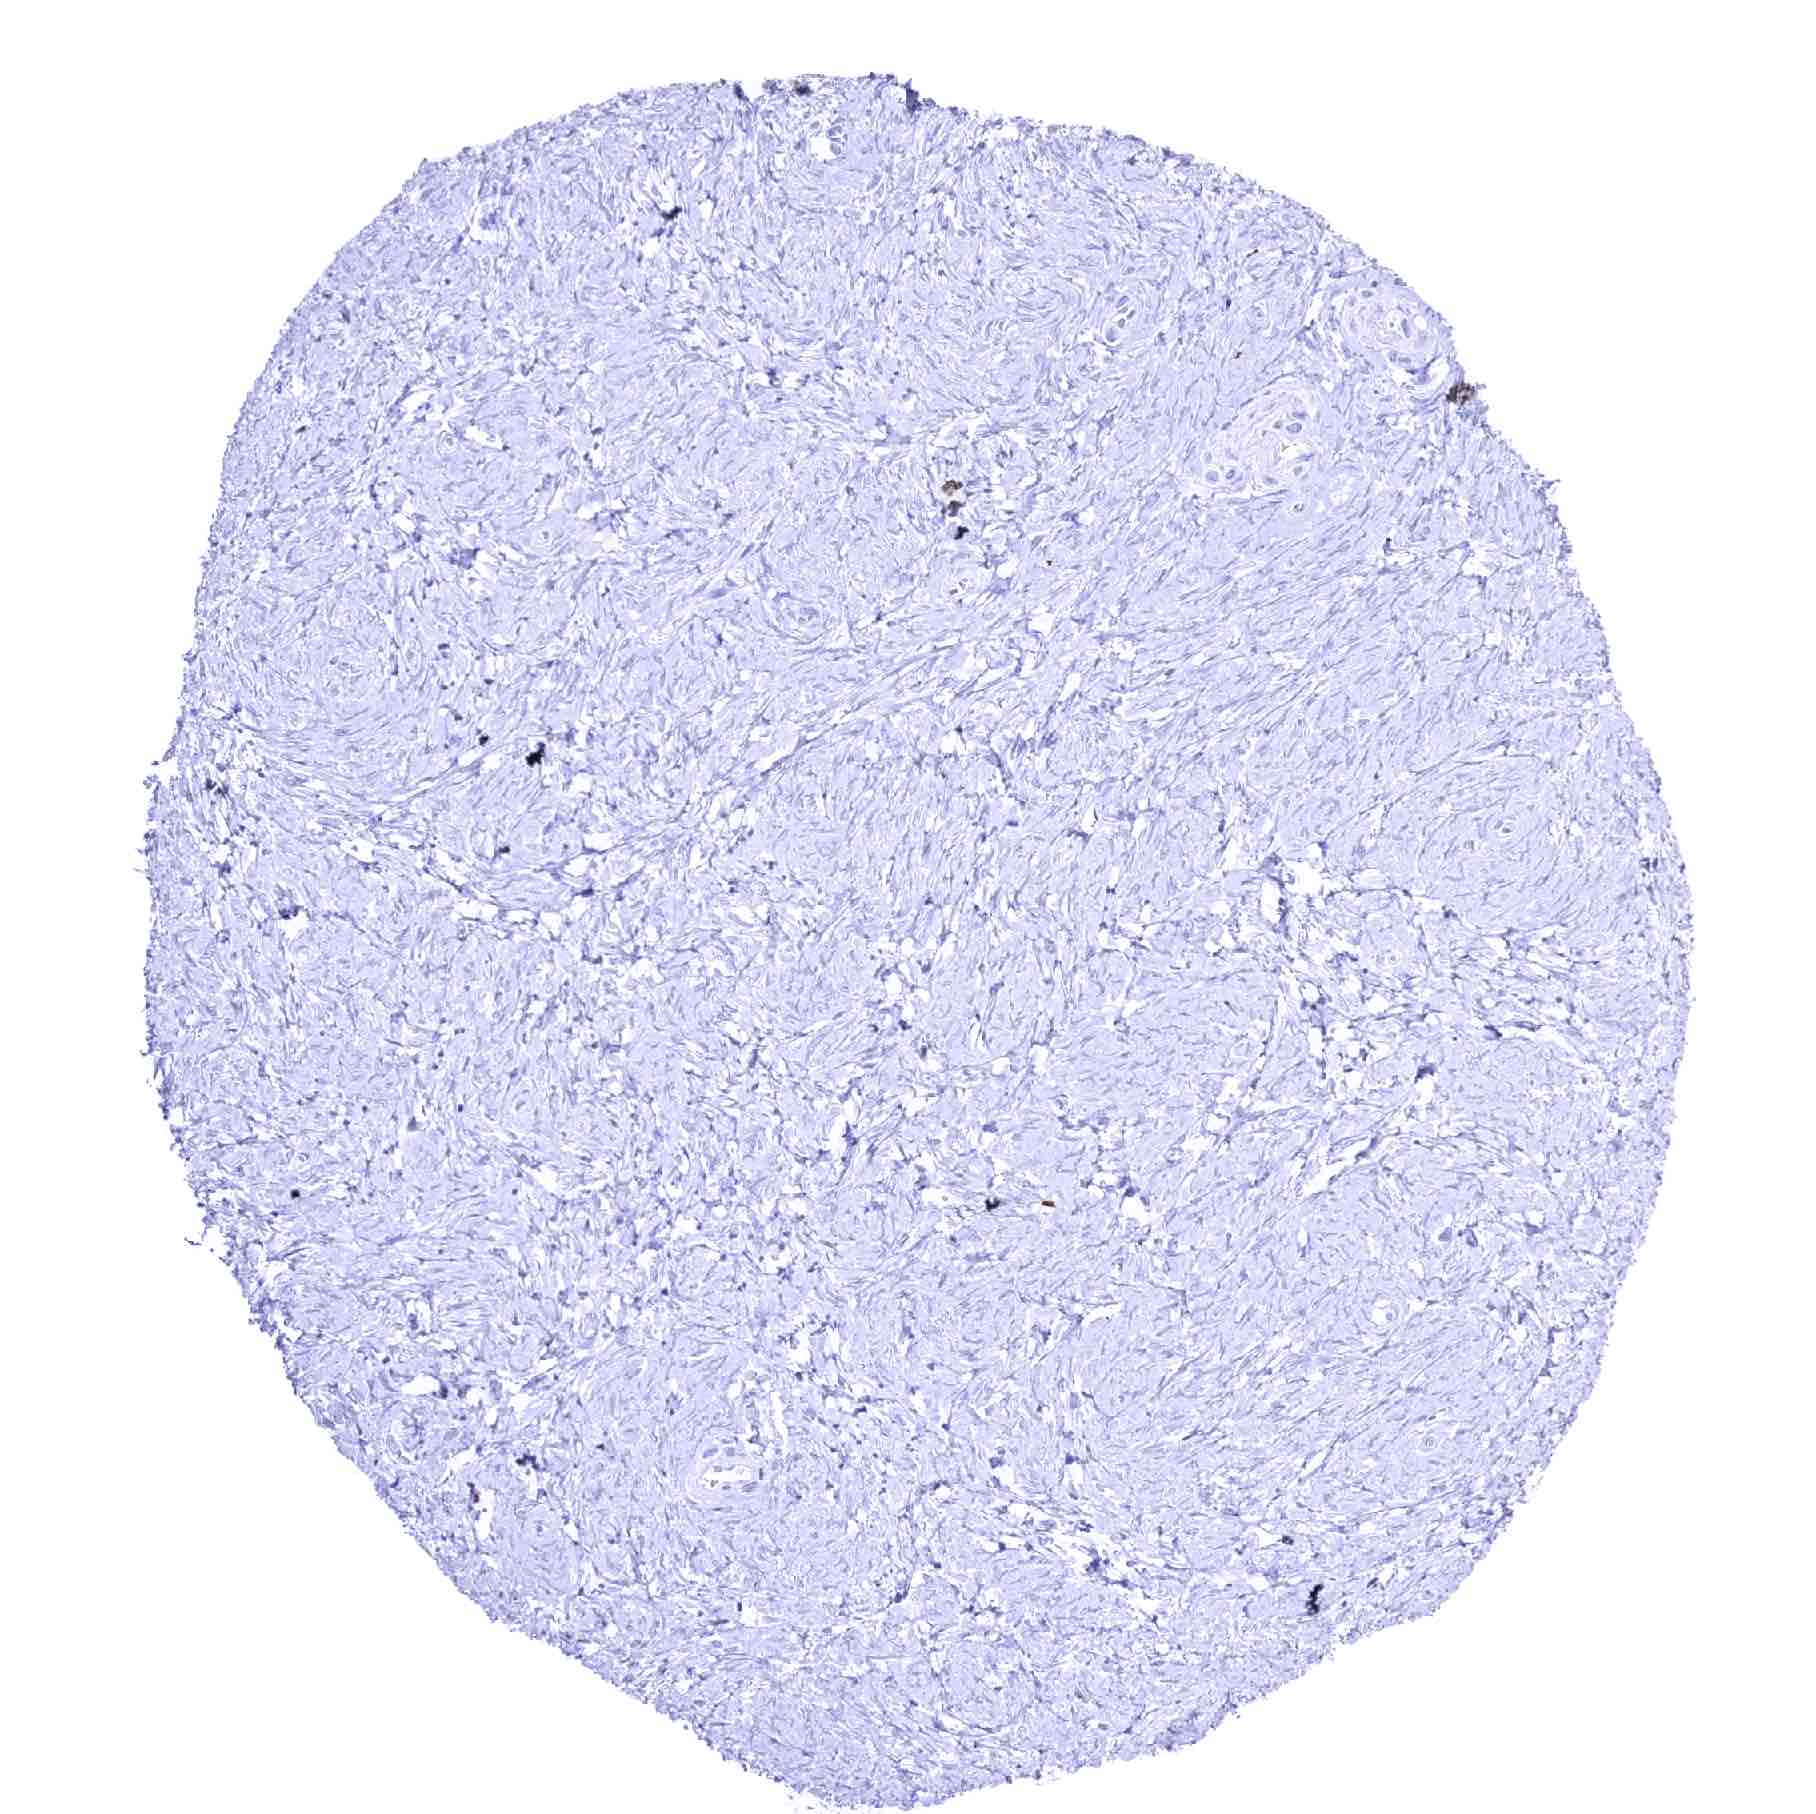

Uterus, myometrium